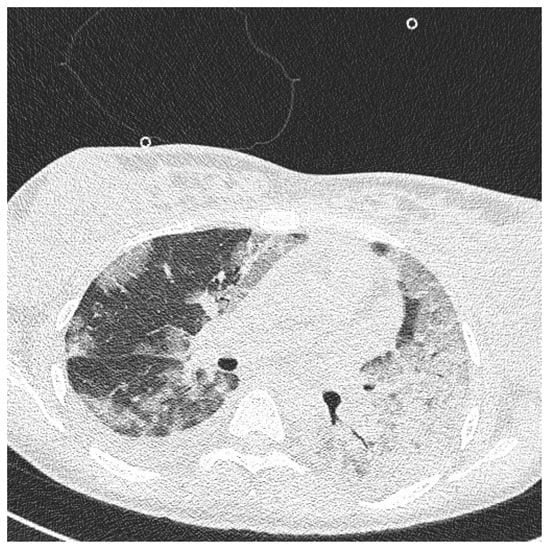

While waiting for the results of laboratory tests, a control cardiotocographic (CTG) recording was made. During the CTG recording, the foetal heart rate was found between 140 and 160 bpm. Within approximately 25 min of recording, reduced short-term variability with single decelerations and no acceleration was found—a pathological record that may suggest foetal hypoxia (Figure 1).

Figure 1. Cardiotocography recording in a patient 1—normal baseline, reduced variability.